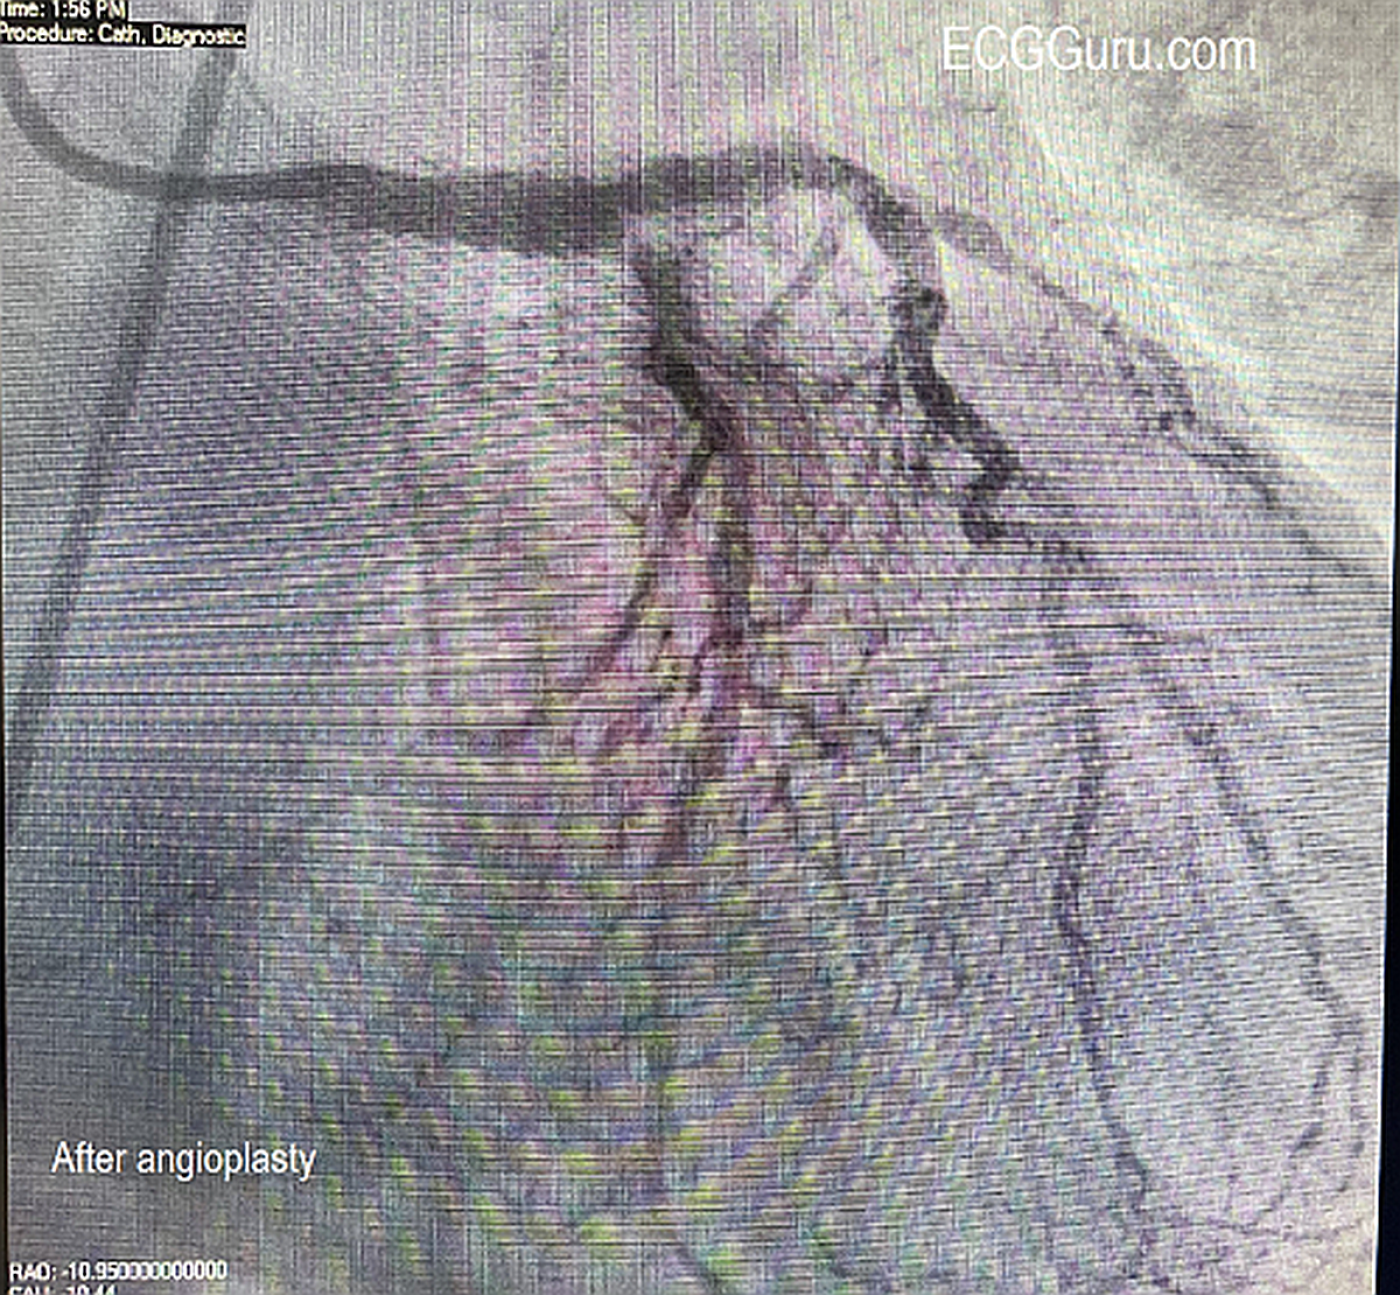

The Cath Lab: In the cath lab, the circumflex artery was found to be totally occluded. When a wire was introduced, circulation opened up, revealing an extensive collateral system from the circumflex to the area usually supplied by the RCA (inferior/posterior wall). The right coronary artery (RCA) was found to have chronic total occlusion (CTO), confirmed by the presence of a collateral system from the circumflex. The arteries show extensive disease. The patient was stabilized with an Impella (mini ventricular pump) placed due to cardiogenic shock. The ECG shows how extensive the damage can be when coronary circulation is relying on one coronary artery system (LCA) to supply the entire heart, and that a large part of that supply (circ) is acutely occluded.

The Outcome: The patient went to surgery for five-vessel coronary artery bypass graft. He did well, and three days later he was awake, alert, having had all central lines, ventilator and ventricular pump removed.